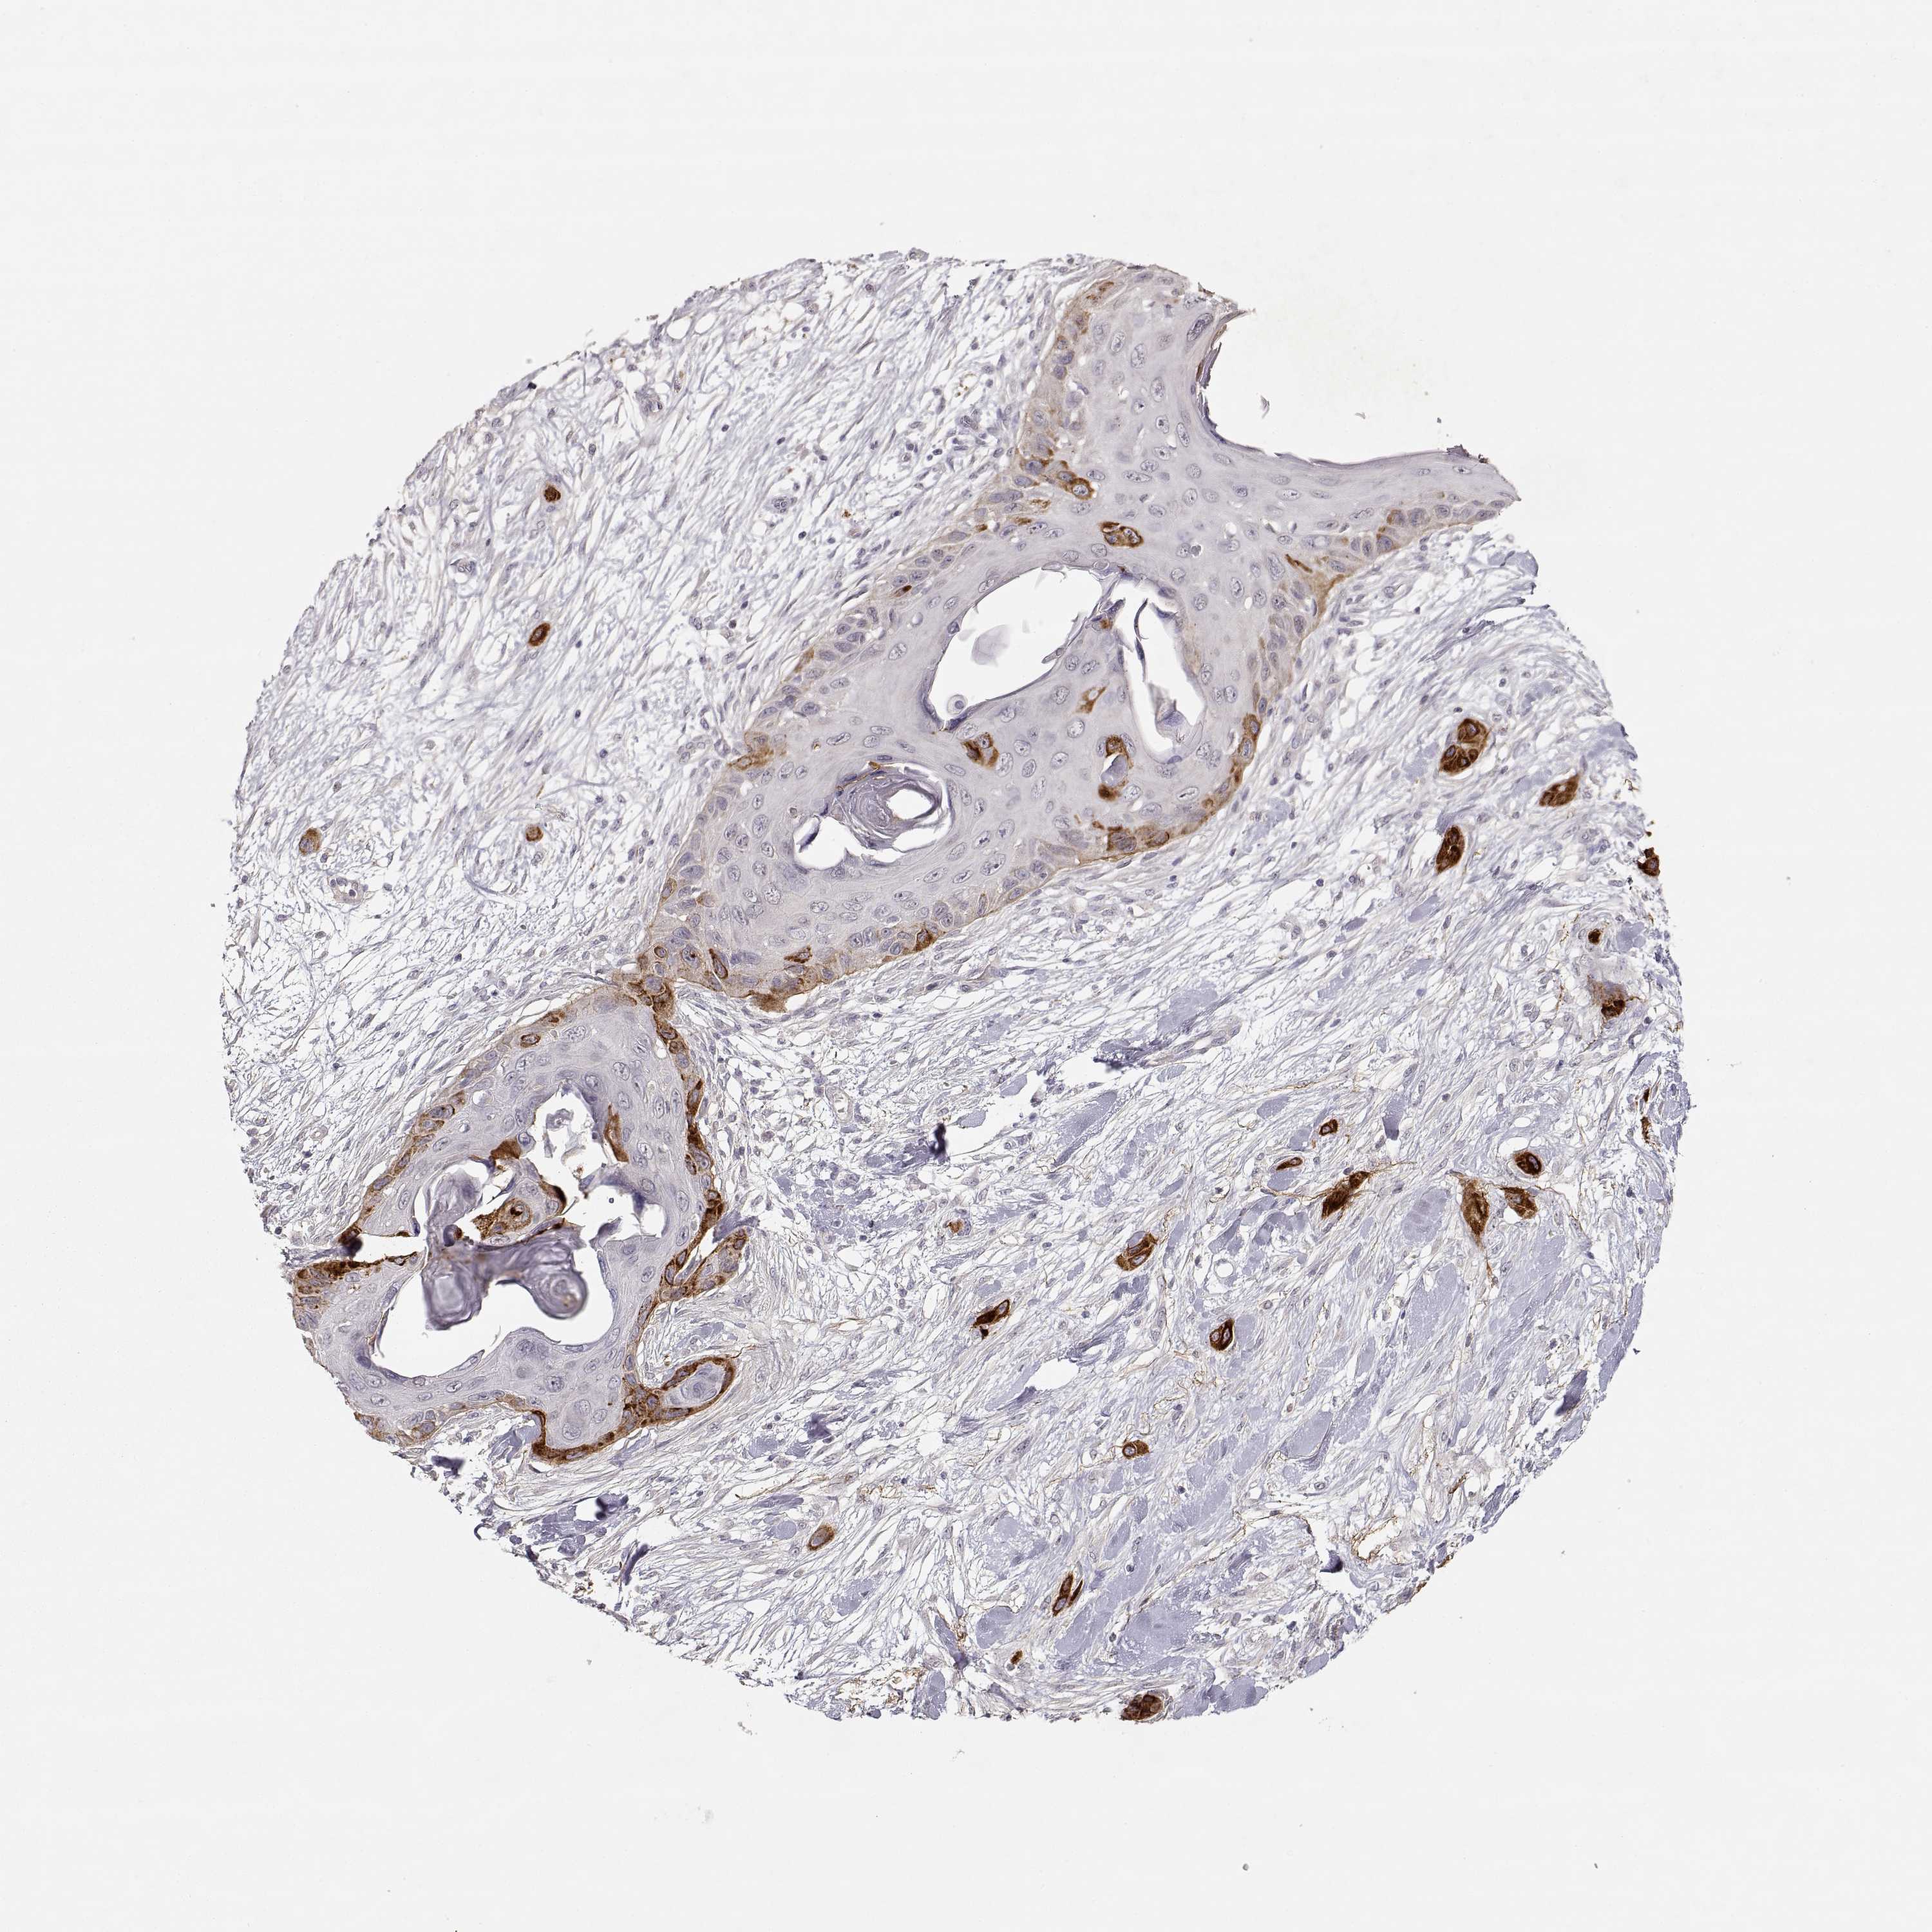

Basal cell and squamous cell cancer

SKIN CANCER - Protein expressioni

A mouse-over function shows sample information and annotation data. Click on an image to view it in a full screen mode. Samples can be filtered based on level of antibody staining by selecting one or several of the following categories: high, medium, low and not detected. The assay and annotation is described here.

Antibody stainingi

Antibody staining in the annotated cell types in the current human tissue is reported as not detected, low, medium, or high, based on conventional immunohistochemistry profiling in selected tissues. This score is based on the combination of the staining intensity and fraction of stained cells.

Each image is clickable and will lead to virtual microscopy that enables deeper exploration of all samples and also displays staining intensity scores, fraction scores and subcellular localization as well as patient and tissue information for each sample.

Antibody CAB004257

Antibody CAB078165

Basal cell carcinoma

Squamous cell carcinoma, NOS